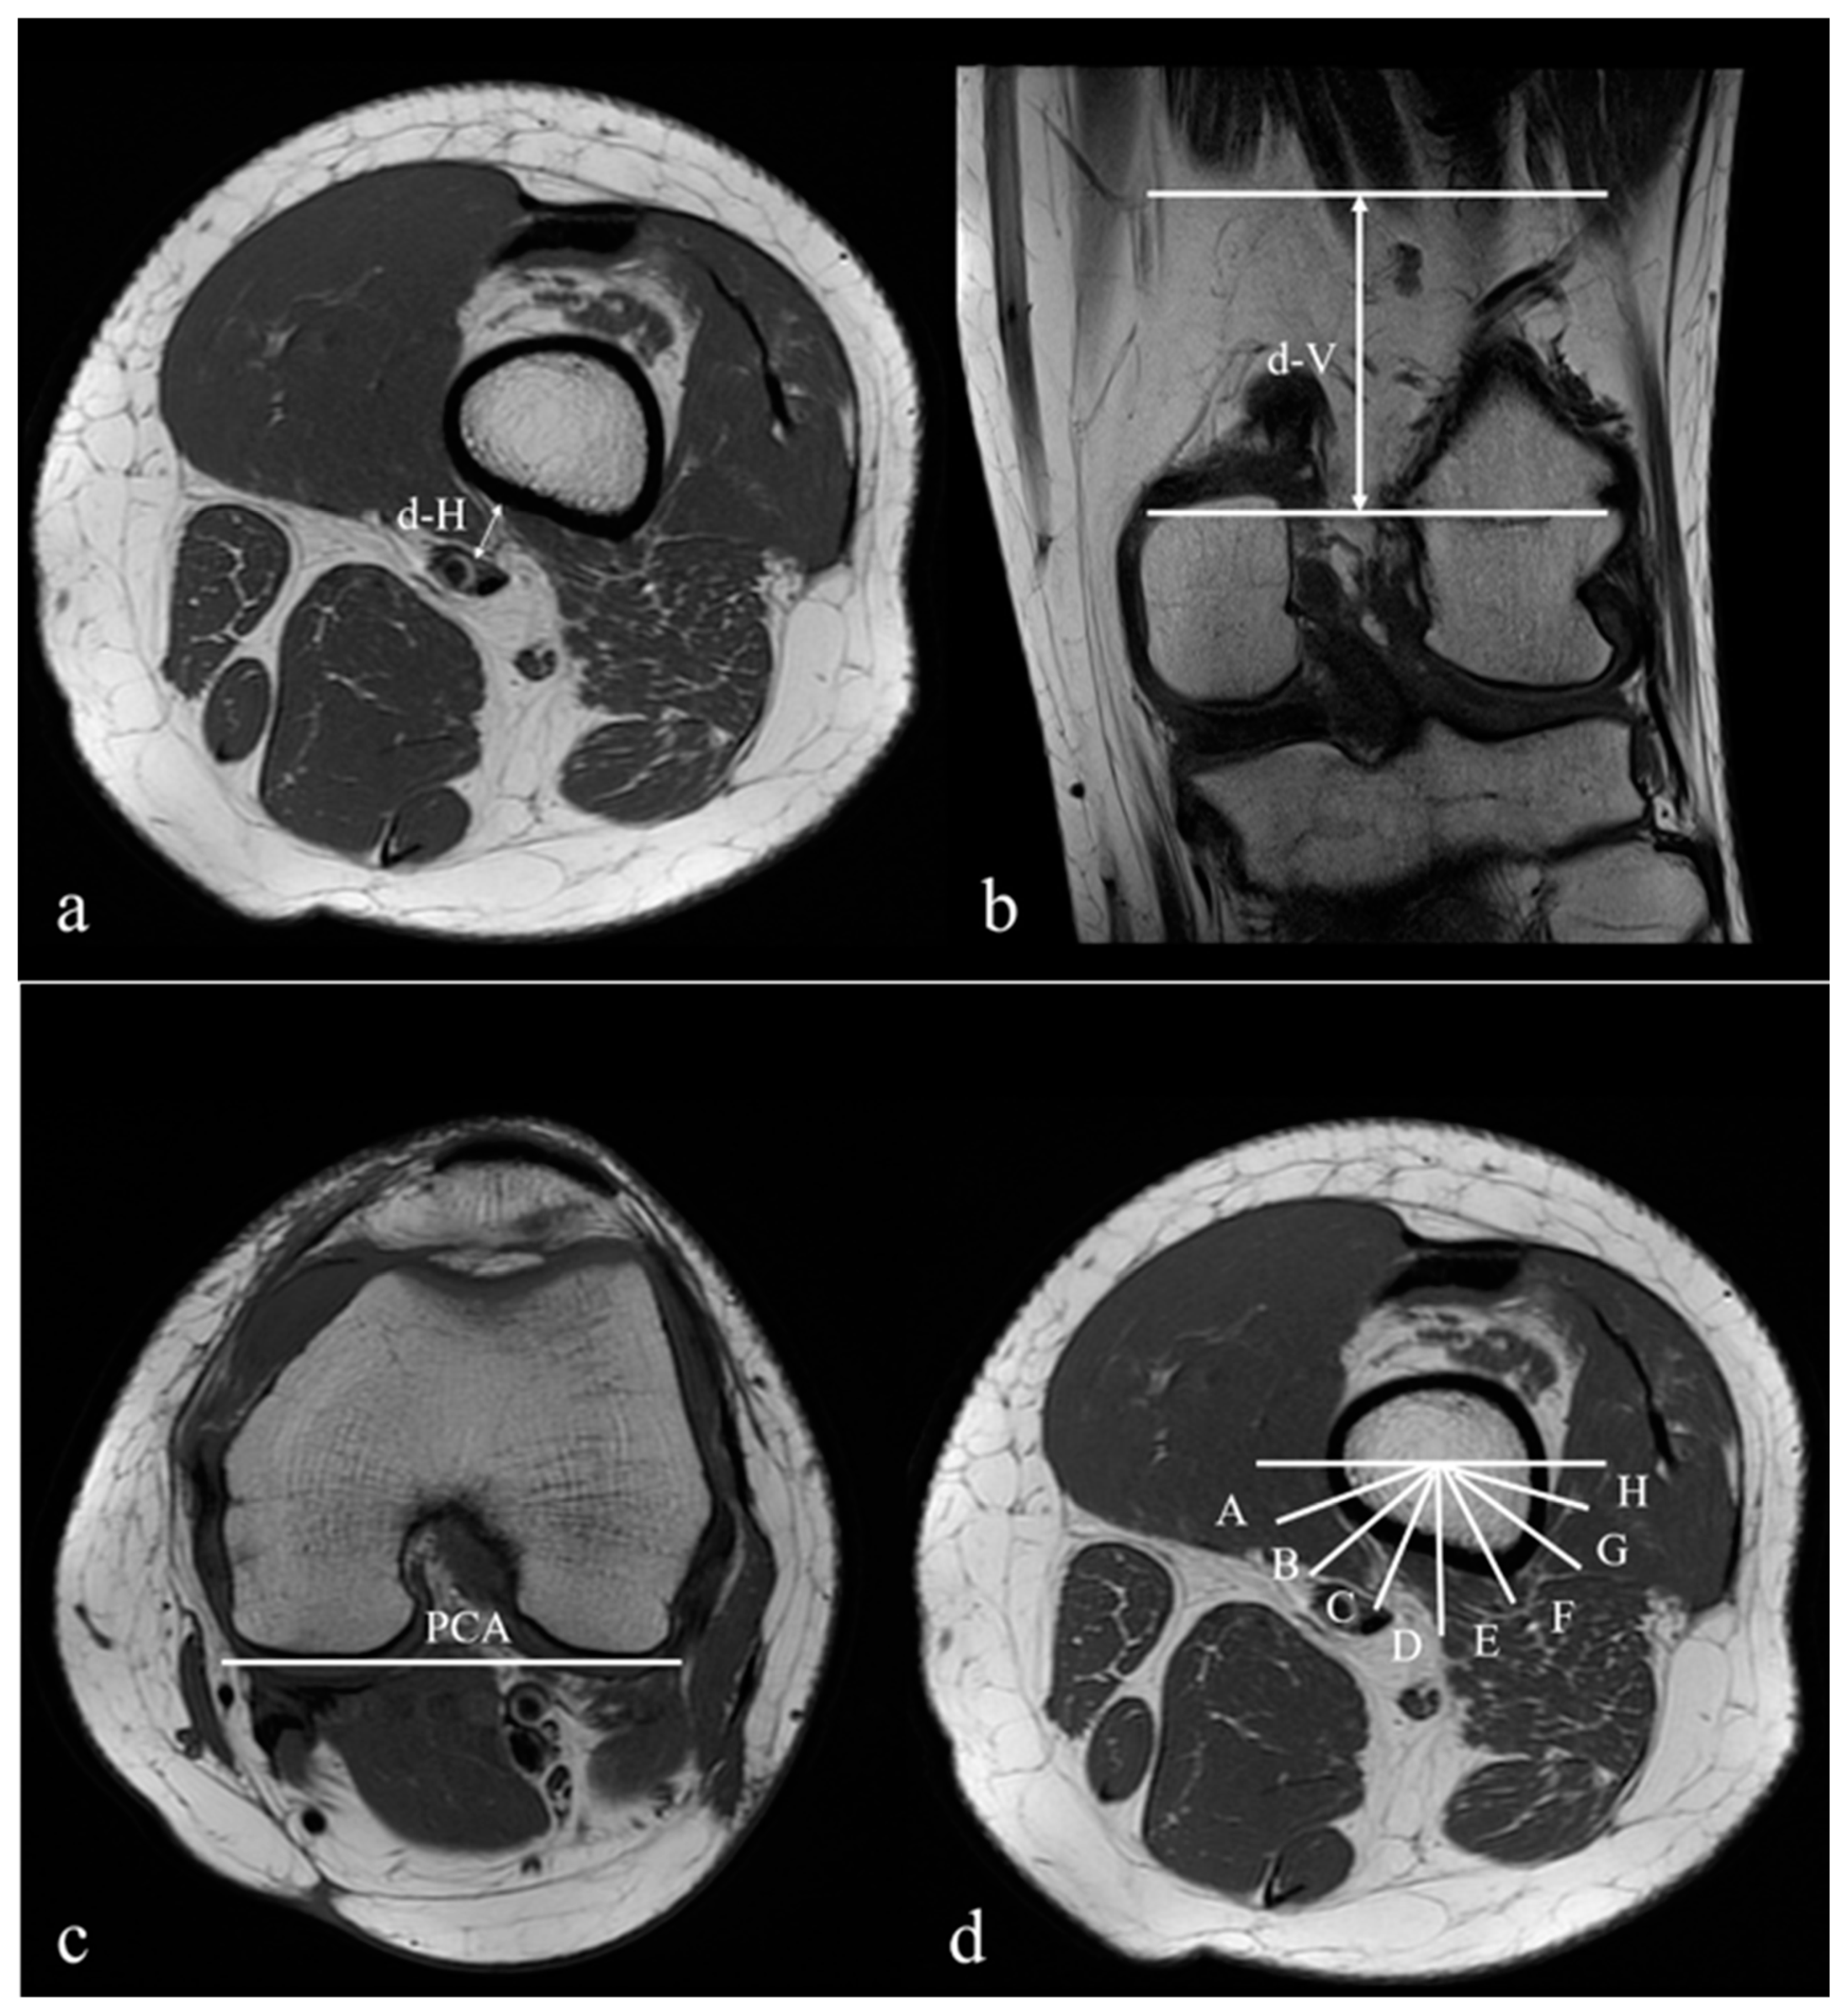

| d-H (mm) | 7.92 ± 3.42 | 6.76 ± 2.86 | 0.010 |

| d-V (mm) | 61.79 ± 9.39 | 51.54 ± 10.49 | <0.001 |